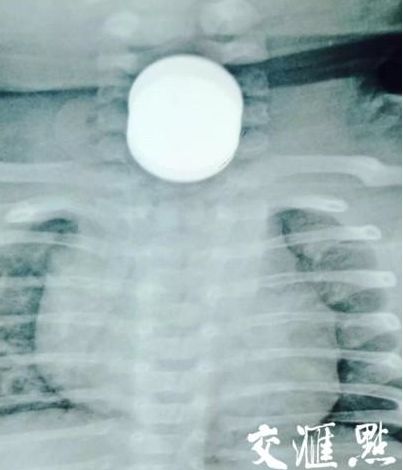

南京一两月大婴儿被两岁贪玩哥哥喂下3枚硬币